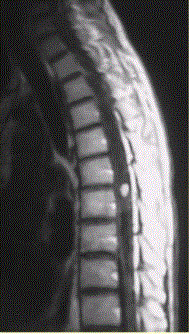

问题 患者女,45岁,胸部不适。影像学检查结果如下图所示。 对病变定位、定性诊断有价值的征象为

选项 A.脊椎增粗 B.邻近蛛网膜下腔变窄 C.病变边界清晰 D.病变特点为一个大囊,其内见一明显强化的结节影 E.病灶内有分隔 F.病灶内可见明显结节样强化

答案 ABCDF